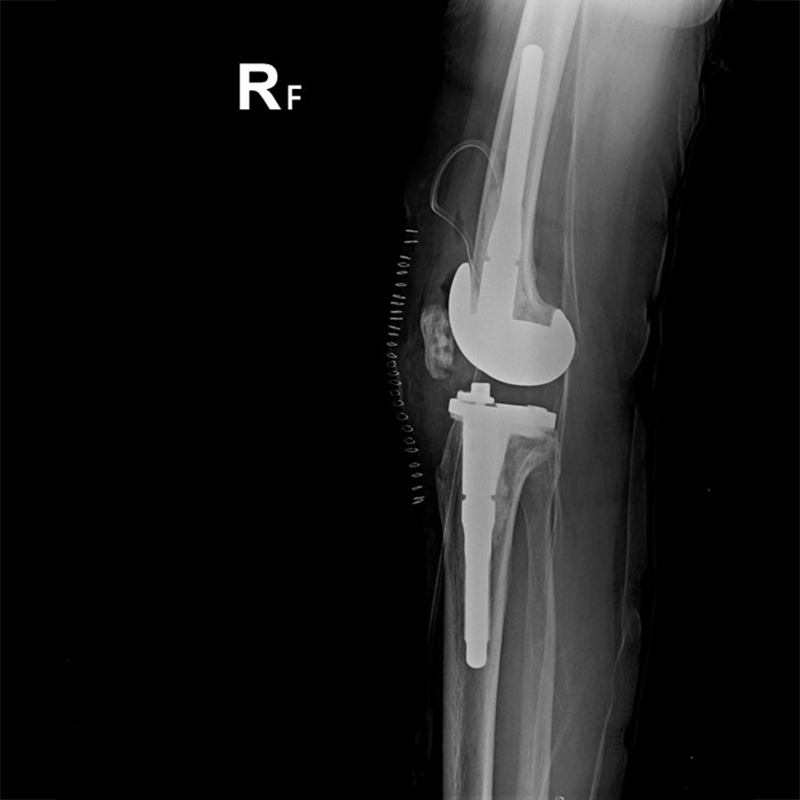

外院失敗本院再置換 首頁 案例分享 膝關節手術 外院失敗本院再置換 蕭女士 69歲 術前 術後 81歲 林女士 術前 術後 蕭女士 69歲 術前 術後 鄒女士 69歲 術前 術後 李女士 74歲 術前 術後 吳女士 71歲 術前 術後 謝女士 65歲 術前 術後